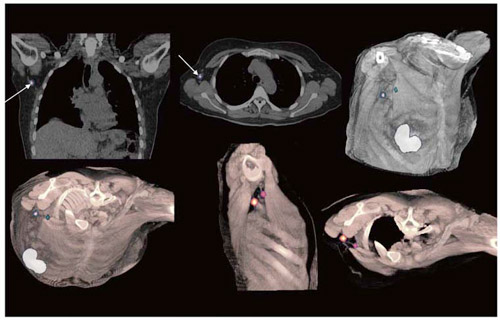

現在,SPECT装置は乳がん領域において,術後フォローアップの骨シンチ検査で広く使われていますが,治療方針決定に用いるセンチネルリンパ節転移イメージングにも使われています。これまで,SPECT装置ではセンチネルリンパ節転移と考えられるRI集積部位の位置情報を正確に検出することが困難であり,また保険適用外であったため,検査を実施することが非常に困難でした。しかし,この臨床用マルチスライスCT搭載型のSPECT・CT装置の登場により,RI集積部位を正確に検出することが可能となりました。そして2010年4月より,センチネルリンパ節生検が保険適用となり,このSPECT・CT装置を用いたイメージングが乳がん治療方針決定に貢献することが期待されています。

センチネルリンパ節転移の検出(画像ご提供: Radiology Clinic Parkway Hospitals, Singapore)

センチネルリンパ節転移の検出

(画像ご提供: Radiology Clinic Parkway Hospitals, Singapore)